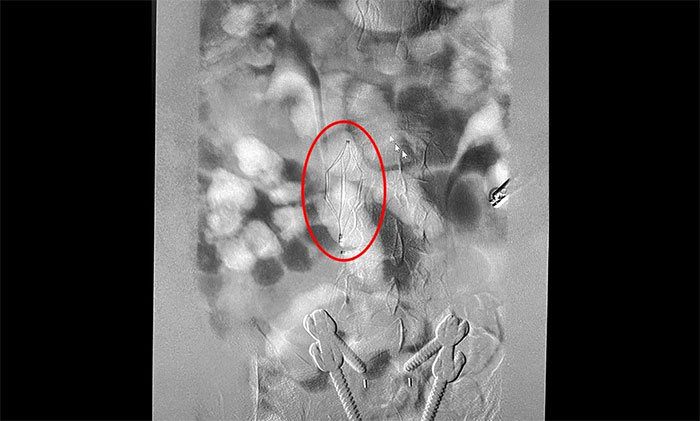

12月15日,席剛明教授在王貴平博士及介入團(tuán)隊(duì)協(xié)助下順利行將一個(gè)形似傘狀的人工濾器經(jīng)患者右側(cè)股靜脈穿刺迅速置入腎靜脈下方,“網(wǎng)”住了通往心血管和肺部的致命栓子,阻擋血液栓子進(jìn)入肺動(dòng)脈,及時(shí)挽救了患者生命。之后對(duì)病變血管進(jìn)行了血栓抽吸術(shù),及接觸性溶栓,抽出了大量血栓,復(fù)查下肢造影示血栓基本消失,下肢靜脈血管再通,整個(gè)手術(shù)順利完成。術(shù)后,患者下肢腫脹好轉(zhuǎn)。

▲ 下腔靜脈濾器順利置入

下腔靜脈濾器置入是為了預(yù)防下腔靜脈系統(tǒng)栓子脫落引起肺栓塞而設(shè)計(jì)的一種裝置,分為永久性和可回收兩種。可回收濾器可經(jīng)健側(cè)股靜脈、亦可經(jīng)頸內(nèi)靜脈置入。該手術(shù)通過(guò)濾器輸送器,將濾器在X線透視下送入,確定位置無(wú)誤后,后撤輸送器直至濾器彈開(kāi)、釋放。